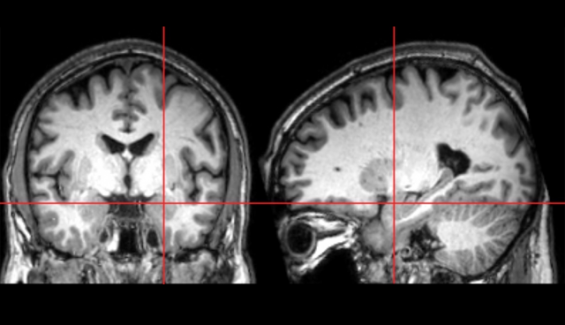

Los hallazgos del nuevo estudio en el American Journal of Psychiatry, que utilizó imágenes por resonancia magnética (IRM), muestran que el crecimiento excesivo comienza entre los 6 y los 12 meses de edad, antes de que emerjan por completo las características del autismo, lo que podría permitir la identificación más temprana de esta condición.

Los autores plantean la hipótesis de que estas alteraciones tempranas en el procesamiento de la información visual y sensorial pueden generar un mayor estrés en la amígdala, lo que lleva a su crecimiento excesivo.

“Estamos cada vez más cerca de comprender por qué ocurre el autismo, al aprender más sobre las alteraciones del crecimiento cerebral en las primeras etapas del desarrollo, en este caso, cómo el crecimiento de la amígdala puede verse influenciado por las dificultades tempranas del procesamiento sensorial y, por el contrario, cómo las alteraciones del crecimiento de la amígdala pueden influir en la interacción de un bebé con su ambiente”, dice Stephen Dager, profesor de radiología en la Facultad de Medicina de la Universidad de Washington y profesor adjunto de bioingeniería.